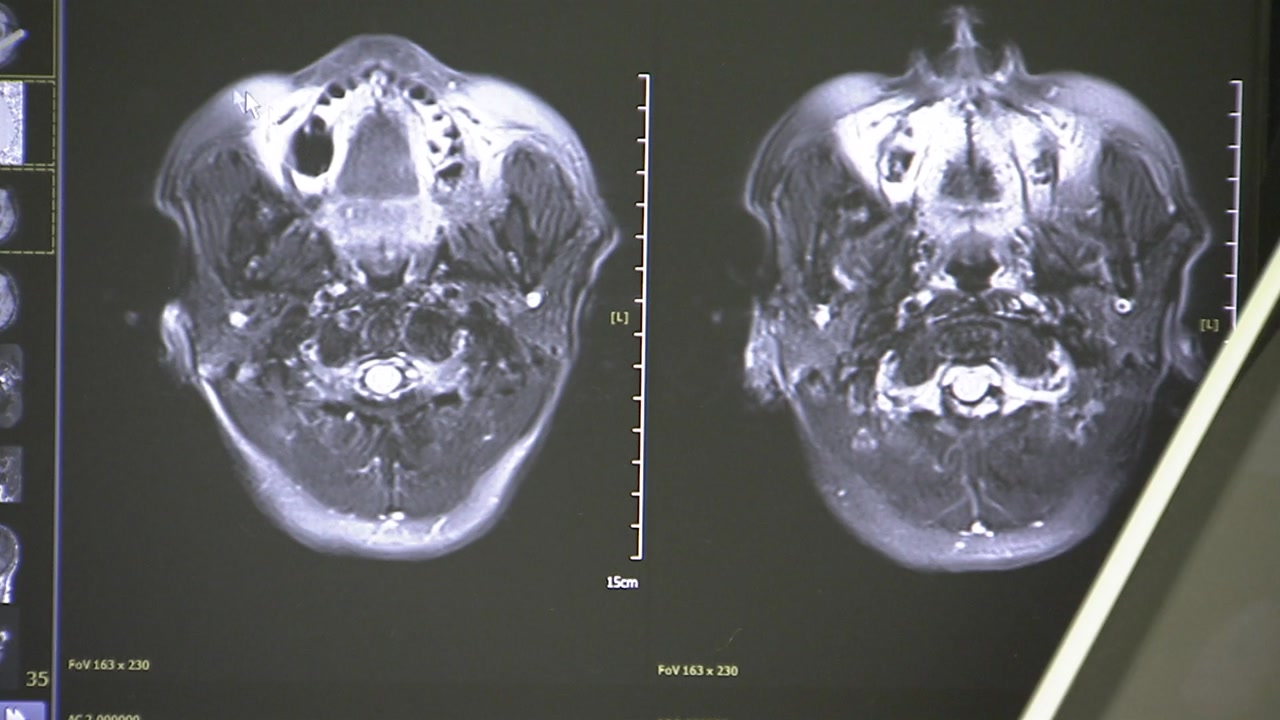

이런 어르신들을 위해 광주치매코호트연구단은 지난 13년 동안 모두 2만 2천여 명의 생체 빅데이터를 확보했습니다.

증상이 없는 60세 이상 어르신들의 혈액을 채취해 언제 치매에 걸릴지를 예측하기 위해서입니다.

[이건호 / 조선대학교 교수, 광주치매코호트연구단장 : 치매 증세를 나타내게 되면 5년 전, 10년 전 혈액 샘플을 통해서 치매 예측이 가능한지를 직접 확인해 볼 수 있다는 점에서 굉장히 연구의 중요한 의미가 있다고 말씀드릴 수 있습니다.]

[이건호 / 조선대학교 교수, 광주치매코호트연구단장 : 치매 정밀 진단을 통해서 치매 고위험군을 발굴하고 이분들을 대상으로 장기 추적을 해왔기 때문에 이제는 치매 증세가 오기 전에 치매 진행을 예측할 수 있는 기술의 확보가 가능해졌다….]